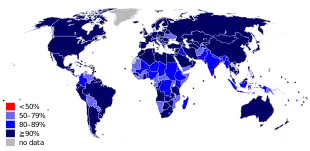

The measles vaccine is effective at preventing the disease, is exceptionally safe, and is often delivered in combination with other vaccines.[7][18] Vaccination resulted in an 80% decrease in deaths from measles between 2000 and 2017, with about 85% of children worldwide having received their first dose as of 2017.[14] Measles affects about 20 million people a year,[3] primarily in the developing areas of Africa and Asia.[7] It is one of the leading vaccine-preventable disease causes of death.[19][20] In 1980, 2.6 million people died from measles,[7] and in 1990, 545,000 died due to the disease; by 2014, global vaccination programs had reduced the number of deaths from measles to 73,000.[21][22] Despite these trends, rates of disease and deaths increased from 2017 to 2019 due to a decrease in immunization.[23][24][25]

In developing countries where measles is common, the World Health Organization (WHO) recommends two doses of vaccine be given, at six and nine months of age. The vaccine should be given whether the child is HIV-infected or not.[67] The vaccine is less effective in HIV-infected infants than in the general population, but early treatment with antiretroviral drugs can increase its effectiveness.[68] Measles vaccination programs are often used to deliver other child health interventions as well, such as bed nets to protect against malaria, antiparasite medicine and vitamin A supplements, and so contribute to the reduction of child deaths from other causes.[69]

Measles is extremely infectious and its continued circulation in a community depends on the generation of susceptible hosts by birth of children. In communities that generate insufficient new hosts the disease will die out. This concept was first recognized in measles by Bartlett in 1957, who referred to the minimum number supporting measles as the critical community size (CCS).[92] Analysis of outbreaks in island communities suggested that the CCS for measles is around 250,000.[93] To achieve herd immunity, more than 95% of the community must be vaccinated due to the ease with which measles is transmitted from person to person.[29]

In 2011, the WHO estimated that 158,000 deaths were caused by measles. This is down from 630,000 deaths in 1990.[94] As of 2018, measles remains a leading cause of vaccine-preventable deaths in the world.[19][95] In developed countries the mortality rate is lower, for example in England and Wales from 2007 to 2017 death occurred between two and three cases out of 10,000.[96] In children one to three cases out of every 1,000 die in the United States (0.1–0.2%).[97] In populations with high levels of malnutrition and a lack of adequate healthcare, mortality can be as high as 10%.[7][98] In cases with complications, the rate may rise to 20–30%. In 2012, the number of deaths due to measles was 78% lower than in 2000 due to increased rates of immunization among UN member states.[29]

Even in countries where vaccination has been introduced, rates may remain high. Measles is a leading cause of vaccine-preventable childhood mortality. Worldwide, the fatality rate has been significantly reduced by a vaccination campaign led by partners in the Measles Initiative: the American Red Cross, the United States CDC, the United Nations Foundation, UNICEF and the WHO. Globally, measles fell 60% from an estimated 873,000 deaths in 1999 to 345,000 in 2005.[100] Estimates for 2008 indicate deaths fell further to 164,000 globally, with 77% of the remaining measles deaths in 2008 occurring within the Southeast Asian region.[101] There were 142,300 measles related deaths globally in 2018, of which most cases were reported from African and eastern Mediterranean regions. These estimates were slightly higher than that of 2017, when 124,000 deaths were reported due to measles infection globally.[102]